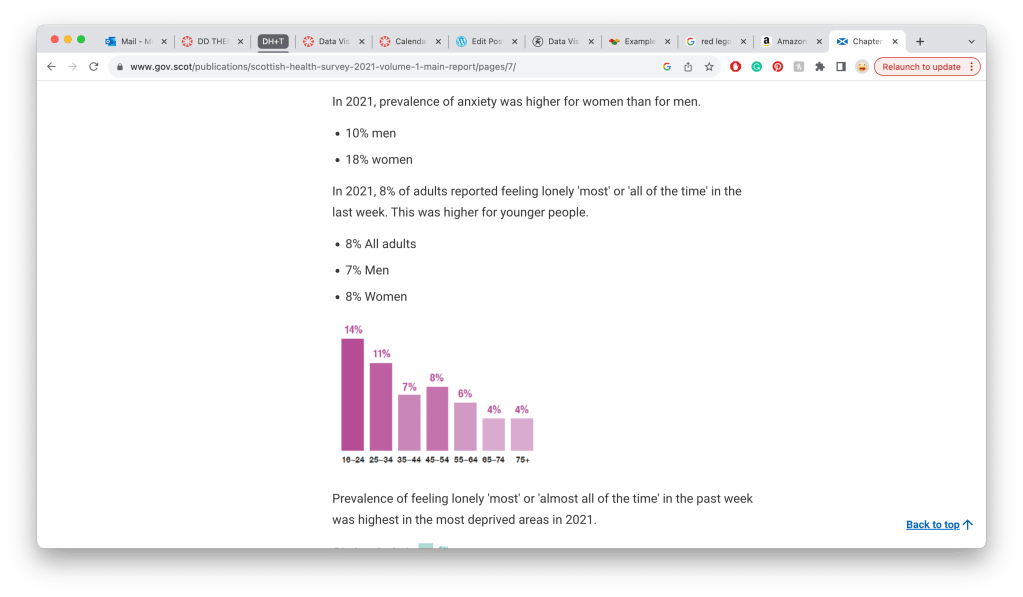

https://www.gov.scot/publications/scottish-health-survey-2021-volume-1-main-report/pages/7/